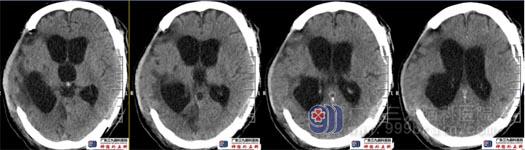

术后复查头颅CT示左侧额颞顶部颅骨修补形态满意,术区未见出血。